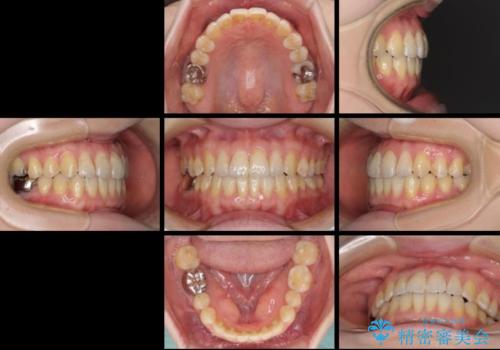

前歯のデコボコを治したい インビザラインによる矯正治療

- 前歯のデコボコを治したいとのことで来院された患者様です。

上下顎ともに歯列全体の後方移動とIPR(歯と歯の間を削る)によってデコボコが解消するように設計し、インビザラインにより治療を行うこととしました。

1日22時間の装着時間をほとんど達成することができず、治療には当初予定の2倍以上の期間を要することとなりました。